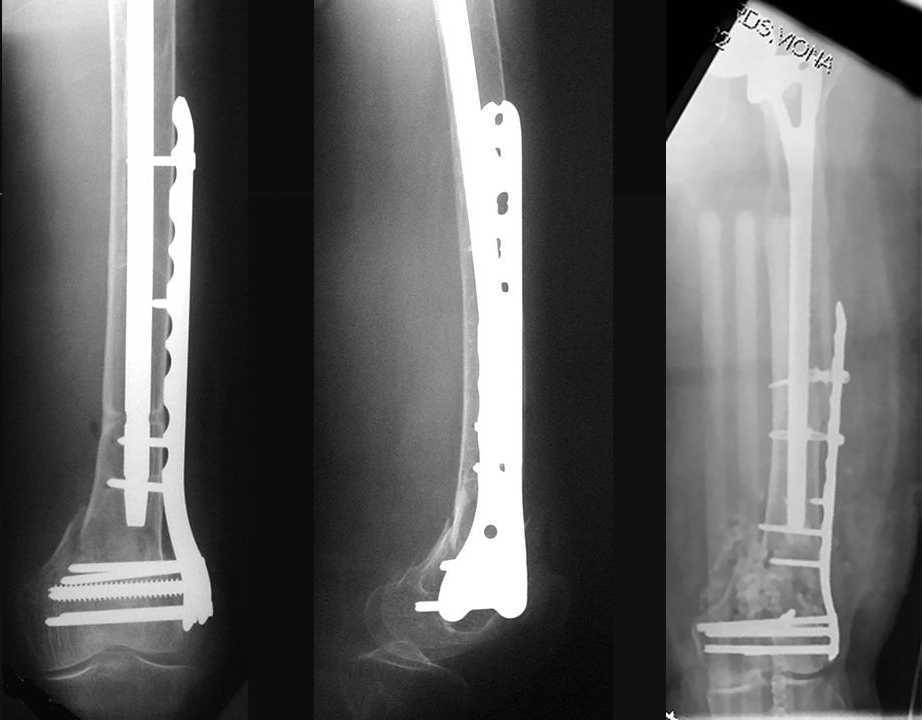

4. We could treat this fracture like there is no a nail - new locking plates allow for secure fixation.... two similar cases are attached...

Images sent by Professor Kanlic look nice, very good job. Excellent achorage in distal fragment. However, unicortical screwing or bicortical

makes a difference, also for locked screws. Proximal fragment unicortical fixation may present stability not easlily predictable. Certainly its stability for wheelchair should be sufficient. Full weight bearing can not be mentioned for this case. If minimal bearing is allowed full weight

Our experience with locking plates in osteoporoticbone and weight bearing is that there's no difference with a nail. the old patient start walking with crutches and 20kg weight bearing as the general conditions are good as for the nail. In this case 13 holes LISS with at least 8 cortex proximally